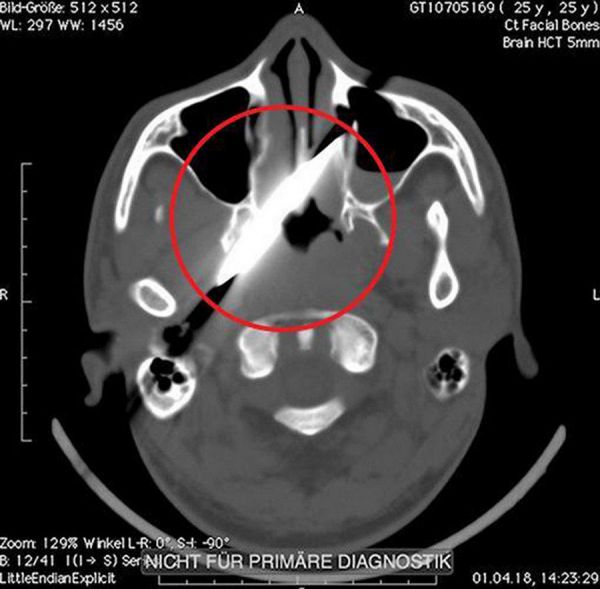

Удар ножом в глаз он получил во время пьяной драки в баре. После этого пострадавший как ни в чем не бывало отправился домой спать. На следующий день мужчине все же пришлось посетить медучреждение. Лезвия он не заметил, однако голова и глаз очень болели. Рентген показал, что нож зашел на 10 см в голову, но не задел ни одной артерии. Врачи даже решили перенести операцию на четыре дня, пока оформлялись необходимые документы.